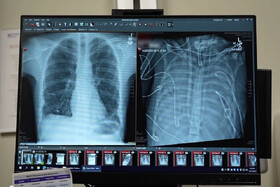

ریه

ریههایتان را با این خوردنیها تمیز کنید!